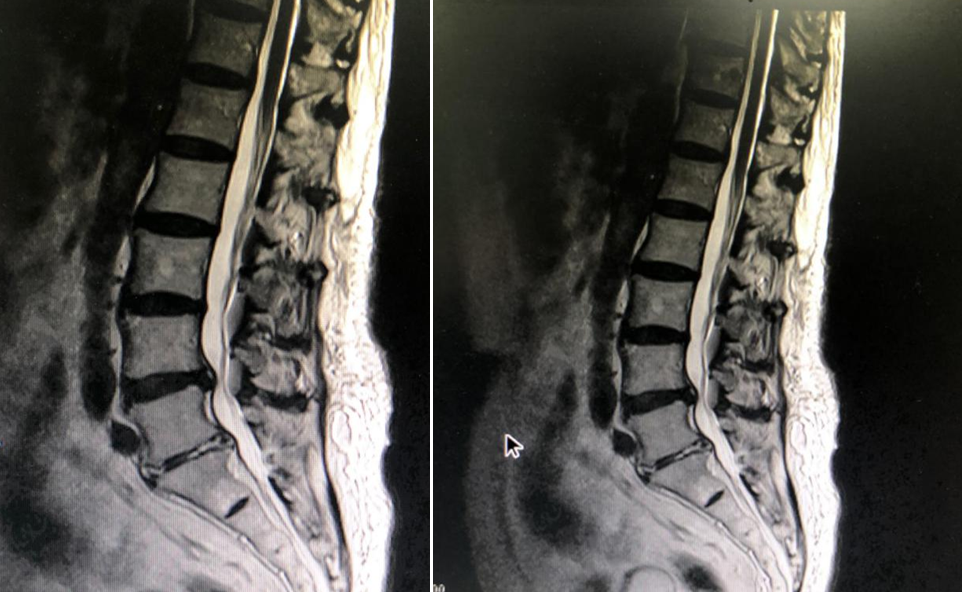

患者术前影像学资料

据介绍,陶老先生合并有高血压、慢性肾功能衰竭、脑梗死等多种疾病。前段时间,陶老先生在家中突然出现右下肢疼痛、双下肢感觉乏力、行走困难,遂慕名来协和深圳医院就诊。三名工程专家及脊柱外科易伟宏主任认真、详细地对老人进行了体格检查,结合陶老先生的影像学资料,考虑椎间盘突出继发椎管狭窄症。